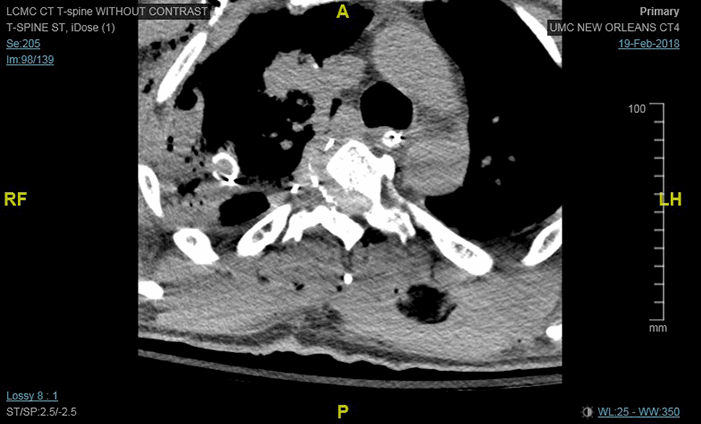

The operative approach was initially an anterior lateral thoracotomy at the fifth intercostal space. Approximately 1 L of hematoma with blood clots were evacuated from the chest. There was obvious active bleeding from the upper lobe of the right lung, which was trapped to the posterior chest wall by the arrow shaft. This area of lung was divided in order to remove it from the arrow shaft and the damaged segment was removed as a wedge using a GIA stapler. The arrow was then visualized penetrating the vertebral column just superior to the arch of the azygos vein. Exsanguination from the arrow tract was apparent, which was suture ligated using 4-0 prolene sutures. The chest cavity was explored, and no further injuries to the lungs or the great vessels were observed. The chest was packed for hemostasis. The tip of the arrow was identified laterally at the level of T4 and penetrated across the midline to the spinal cord. Neurosurgery was consulted to remove a portion of the foreign body traversing the spinal cord. An intra-operative lateral mid-thoracic x-ray revealed that the arrowhead wings were posterior to the spine (Figure 2). The remaining 8 cm of arrow shaft extending from the thoracic cavity was clipped at the level where it entered the vertebral column (Figure 3) and removed from the chest cavity. A wound vacuum dressing was applied over the chest wound.

Figure 2. Intraoperative fluoroscopy image